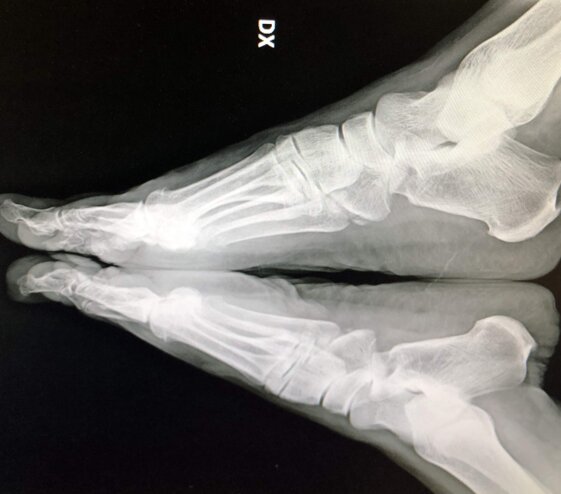

Radiografie post-operatorie in AP e LL di intervento di correzione di Alluce Valgo con tecnica mini-invasiva senza utilizzo di mezzi di sintesi metallici. Per l’osteotomia di correzione del I MT ho utilizzato un pin riassorbibile che quindi non è visulizzabile alle radiografie, mentre per l’osteotomia della prima falange del primo dito non ho utilizzato alcun mezzo di sintesi

Radiografie post-operatorie in AP di due interventi di correzione di Alluce Valgo con tecnica mini-invasiva senza utilizzo di mezzi di sintesi metallici. Per l’osteotomia di correzione del I MT ho utilizzato in entrambi i casi un pin riassorbibile che quindi non è visulizzabile alle radiografie. Nel caso a sinistra per l’osteotomia della prima falange del primo dito non ho utilizzato alcun mezzo di sintesi, nel caso a destra non ho effettuato l’osteotomia in quanto era presente un alluce valgo meno grave

In alto a sinistra foto pre-operatoria piede destro in pz con Alluce Valgo.

In alto a destra ed in basso a sinistra radiografie pre-operatorie dei piedi sotto carico in AP e LL. La pz è stata operata con accesso mini-invasivo, per l’osteotomia del I MT non sono stati utilizzati mezzi di sintesi metallici ma un pin riassorbibile; nel caso specifico non ho effettuato l’osteotomia di F1 I dito in quanto la qualità dell’osso non era ottimale